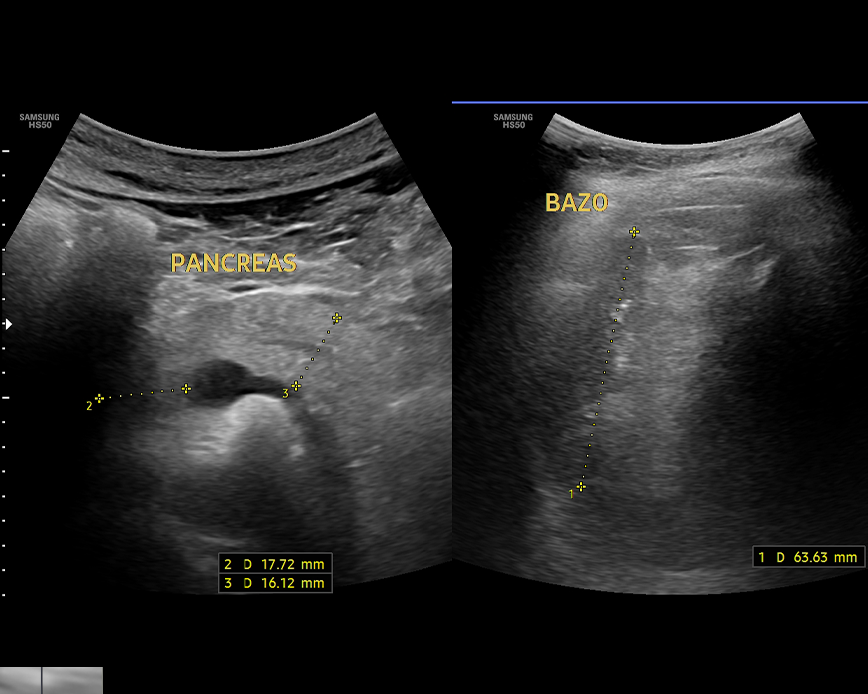

- Evaluación del páncreas

- Evaluación del bazo